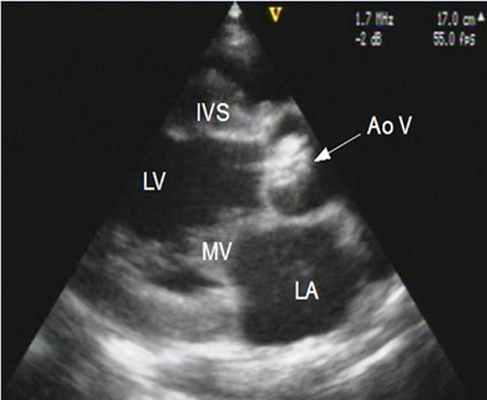

г) Эхокардиография в М-режиме. При эхокардиографии в М-режиме крутизна сегмента EF снижена, размер левого желудочка меньше, чем в норме, и увеличено время диастолической релаксации (правая часть рисунка ниже). Левое предсердие расширено, если нет сброса крови в правое предсердие.

Врожденный митральный стеноз, выявленный при ЭхоКГ в М-режиме вдоль короткой оси сердца из парастернальной позиции датчика. На двумерной эхокардиограмме створки митрального клапана имеют крестообразную конфигурацию и по своей площади существенно уступают размерам полости левого желудочка. Медиальная сосочковая мышца (двойная стрелка) существенно выделяется, в то время как латеральная значительно меньше (одиночная стрелка). При ЭхоКГ в М-режиме крутизна спуска сегмента EF снижена. Митральный стеноз при сканировании в диастолу из апикальной позиции вдоль длинной оси сердца с наложением цветового допплеровского изображения. Стрелкой обозначена передняя митральная створка, которая в диастолу едва открывается. Струя крови через стенозированный митральный клапан имеет характерный вид, напоминающий пламя свечи, и повышенную скорость.